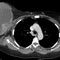

Delayed total body images from bone scan (Figure 4) revealed age-appropriate physiologic distribution of tracer activity throughout the skeletal system; however, a rim of increased tracer activity outlined the right breast mass, consistent with inflammatory process. The CT of the chest, abdomen and pelvis with contrast (Figure 5) discovered multiple hyperdense and cavitary nodules within the lungs, findings suspicious for metastatic disease. Subsequent pulmonary nodule fine needle aspiration confirmed metastatic disease. An MRI was not performed secondary to the large size of the breast mass.